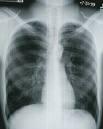

March 5, 2009 – Fifty patients who have undergone stereotactic body radiotherapy (SBRT) at Temple University have doubled their chances of surviving early stage lung cancer - and without the conventional radiation regimen or surgery.

SBRT requires only three to eight treatments for lung cancer, not 35 in the typical case of radiation therapy. Although both traditional treatments and SBRT methods involve radiation, SBRT administers large, highly precise doses instead of multiple smaller doses.

But perhaps the most important advantage of SBRT is its effectiveness: Patients who refuse or cannot receive conventional treatments for their lung cancer face a median survival range of nine months. For those who undergo SBRT, the median survival range is more than 32 months. And depending on the size and seriousness of the tumor, the two-year disease free survival, or cure rate through SBRT increases to approximately 81 percent and can reach up to 98 percent, according to findings in the International Journal of Radiation OncologyBiologyPhysics. The cure rate with conventional radiation is closer to 35 percent; SBRT doubles the odds of surviving early stage lung cancer and can actually cure at least half of the patients.